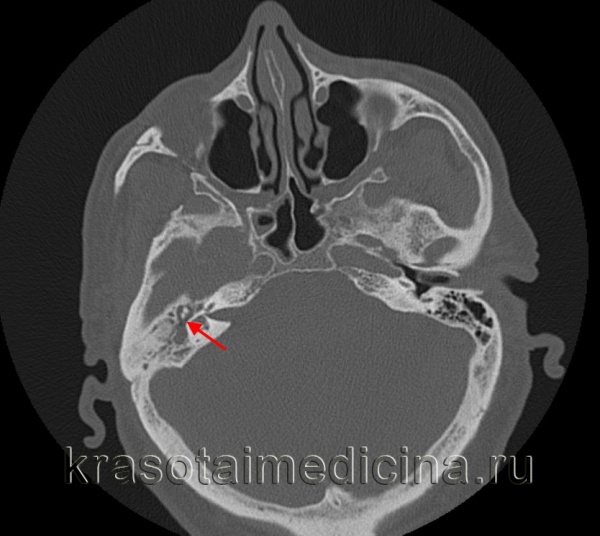

КТ височных костей. Содержимое (гной) в полости среднего уха вокруг слуховых косточек.